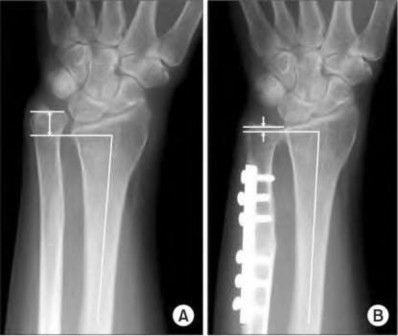

Question 9:

A 30-year-old male sustains a severe midfoot sprain. Radiographs reveal widening between the bases of the first and second metatarsals. The primary ligamentous stabilizer disrupted in this classic Lisfranc injury connects which two osseous structures?

Options:

- Medial cuneiform to 1st metatarsal base

- Medial cuneiform to 2nd metatarsal base

- Middle cuneiform to 2nd metatarsal base

- Lateral cuneiform to 3rd metatarsal base

- Navicular to medial cuneiform

Correct Answer: Medial cuneiform to 2nd metatarsal base

Explanation:

The Lisfranc ligament is the strongest ligament in the tarsometatarsal joint complex. It courses obliquely from the lateral aspect of the medial cuneiform to the medial base of the second metatarsal. It acts as the primary stabilizer of the second metatarsal base. Disruption results in the classic widening between the first and second rays, often with an avulsion fragment ('fleck sign').